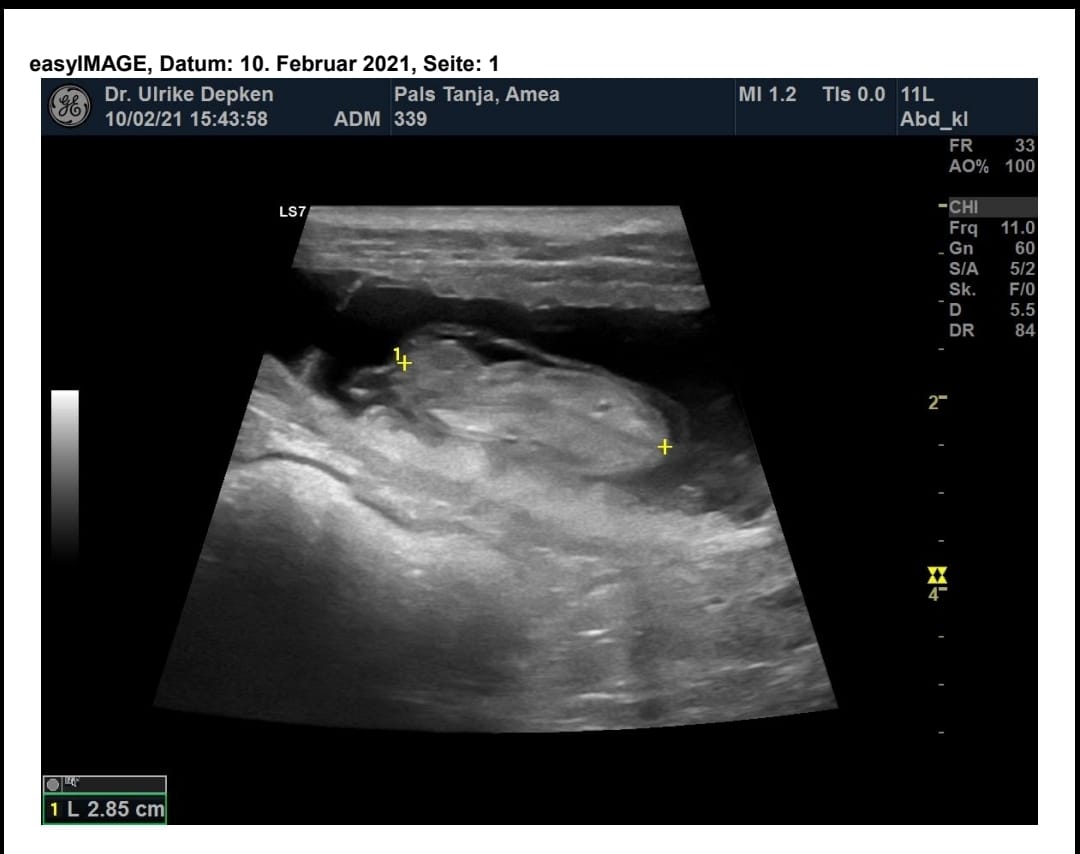

Mi,27.01.2021 waren wir zur Trächtigkeitsuntersuchung. Bei dieser Untersuchung wurde uns mitgeteilt das Amea resorbiert. Die Fruchthöhlen seien leer,heißt es. Am Boden zerstört geben wir die Hoffnung nicht auf und wissen das eine Befruchtung stattgefunden hat. Wir wollen es nicht wahrhaben. Amea wird weiter gut betreut und sondert am 07.02.2021 deutlich klaren, zähen Schleim ab. Das ist ein ganz deutliches Zeichen einer Trächtigkeit. Sehr hoffnungsvoll geht es am 10.02.2021 erneut zum Ultraschall. Tolles Ergebnis! Die Befruchtung hat sehr deutlich spät nach dem Deckakt stattgefunden. Es geht "Prinzessin"gut. Welpen Entwicklung ist wie es um Tag 33 sein soll. Gut 2,85 cm groß. Die kleinen Herzen schlagen.

Überglücklich zeige ich hier das erste Foto von "C"